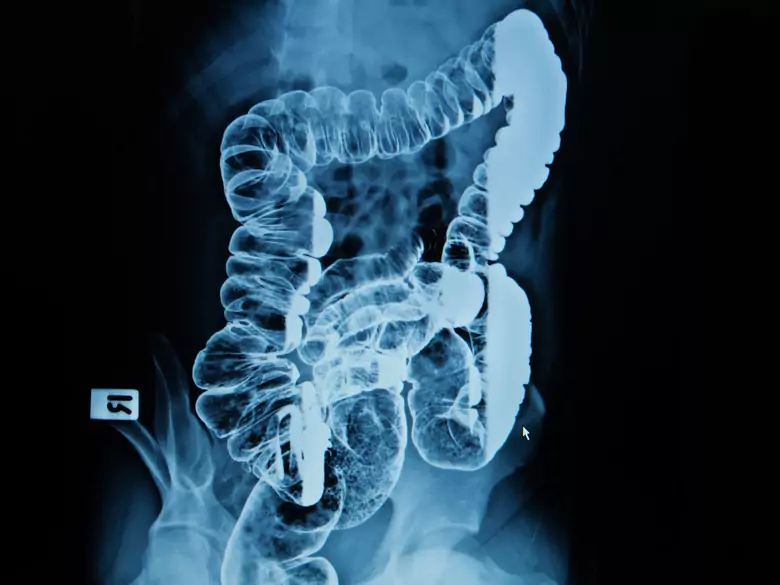

Badanie jelita